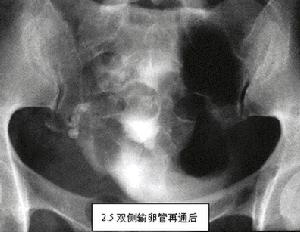

輸卵管發育不全(hypoplasiaofthefallopiantube)常與性腺發育不全、兩性畸形以及其他的生殖道畸形並存。發育不全的輸卵管也稱為幼稚輸卵管,也可見於內生殖器無嚴重病理變化的情況,如僅子宮發育不良。發育不全的輸卵管可表現為實管的輸卵管、索狀的輸卵管以及發育不良的輸卵管,這些都屬於輸卵管發育早期受到不同程度的抑制或阻礙使其不能完全發育的情況。輸卵管發育不良的特點為:輸卵管紆曲、管腔常狹窄、管壁菲薄及壺腹部部分肌層發育不良。在子宮輸卵管碘油造影檢查時可在近傘端壁薄的輸卵管壺腹部形成一個囊,從而導致輸卵管積水或傘端漏斗部水腫狹窄的假象。行腹腔鏡檢查時在擴張的壺腹部可清楚見到流通的藍色液體的閃光,也就是液體可勉強通過管腔的徵象,但在術中未能發現傘端漏斗部有阻塞,亦無明顯的手術矯正適應證。近子宮段的輸卵管發育不良時,由於其管腔狹窄,在子宮輸卵管碘油造影檢查時需增高壓力方能使碘油通過該處,故此處的輸卵管發育不良常常可造成輸卵管峽部梗阻的假象。輸卵管發育不全常伴有一些其他的病理改變,如子宮內膜異位症,副輸卵管,輸卵管傘端過長,卵巢韌帶緊張。輸卵管發育不良的臨床意義主要是生育能力降低,導致生育能力降低的機制大致是輸卵管傘端拾卵功能障礙和卵子在輸卵管中移行障礙所致,但這部分患者中常常有人在未經治療的情況下自然受孕,所以對此到目前為止尚無一個既定的手術或藥物治療方案。有人認為這種發育不良類型的畸形應與壺腹部與峽部的輸卵管梗阻相鑑別,以避免進行不必要的關於不孕症方面的腹腔鏡檢查。